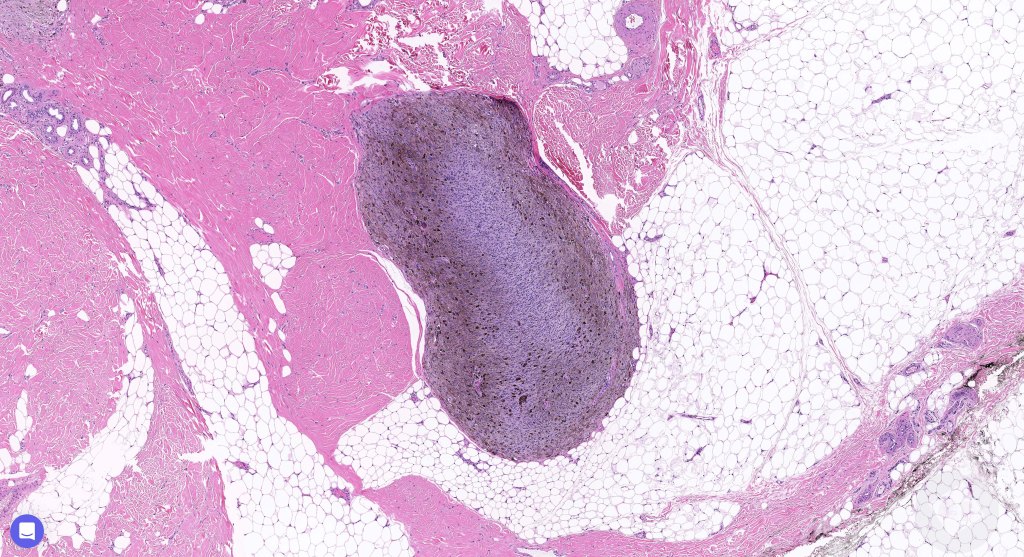

Cellular blue nevus

This uncommon most often devlops on the buttocks, sacrococcygeal region & distal extremities although it may be seen at just about any site. It shows a predilection for females and is diagnosed most often in the 2nd-4th decade. It presents as a blue-black/ or black nodule measuring 1-2 cm in dianeter. Similar to common blue nevus, the cellular variant can be encountered in a wide range of non-cutaneous locations.

Histological features

•Most characteristic is the dumbbell silhouette although a plague morphology may also be encountered

•An alveolar pattern is characteristic particularly with clear cell nodules

•Stromal fibrosis, myxoid change, vascular hyalinization with cyst formation are often seen